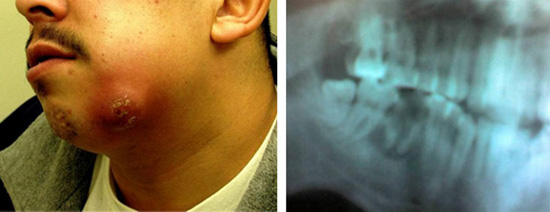

El paciente es un joven de sexo masculino, de buena apariencia. En el examen físico, su temperatura es de 99,2 ° F (37,3 ° C), su presión arterial es 125/87 mm Hg, y su frecuencia cardíaca es de 85 latidos por minuto. El paciente tiene un área difusa de tejido blando, hinchazón y eritema en el lado izquierdo de la parte baja de la mandíbula, se observa una masa de 2 × 2 cm fluctuante en la región submandibular, sin secreción ni formación de costras superficiales. No hay evidencia de trismo o babeo. En el examen intraoral se observa una significante fractura de esmalte en el primer molar inferior izquierdo.